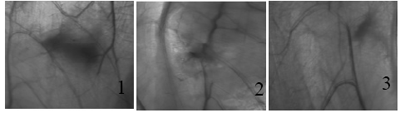

На первые сутки и последующие сроки наблюдений за животными не было обнаружено каких- либо существенных нарушений сроков и процессов заживления ран после произведенного оперативного вмешательства. У всех животных послеоперационные раны зажили первичным натяжением. В срок наблюдения 7 суток. После обнажения косых мышц передней брюшной стенки животных, была заметна область проведенного вмешательства (рис. 2.1). При от-делении и просвечивании лампой передней брюшной стенки животных, у контрольной группы обнаружено затемнение в виде полнокровия с очагами крово-излияния, нарушение русел кровеносных сосудов в области вмешательства. У животных опытной группы четко можно было определить контуры мембраны из пчелиного воска (рис.3.1). В обеих группах, по соседству с зоной вмешательства, имело место некоторое снижение просвечиваемости передней брюшной стенки, что видимо обусловлено развивающимся послеоперационным отеком. Микроскопически регенерационно-грануляционные процессы выражены в контрольной группе реактивно-воспалительной реакцией с новообразованными сосудами, сформи-рованными либо путем почкования сохранившихся, либо без связи с имеющимися сосудами. Участки разволокнения мышечных волокон пронизаны плазматическими клетками и соединительной- грануляционной тканью, представленной полиморфными клетками от эндотелиальных, фибробласти- ческих, гистоцитарных до скопления нейтрофилов и макрофагов, а также сетью волокон, расположенных между сосудами (рис. 4.1). В препаратах опытной группы не обнаруживается макрофагальная реакция, имеющиеся соединительнотканные элементы в основном фибробластические, однако выявляются широкие просветы между мышечными пучками, указывающие на присутствие мембраны (рис. 5.1).

Наблюдения на 15-е сутки после операции мало отличались от результатов, полученных на 7-е сутки. Макроскопически имело место повышение про-зрачности передней брюшной стенки, исчезновение признаков отечности тканей. Область вмешательства у контрольной группы животных выглядела более прозрачной. В микропрепаратах отмечаются умеренные реактивно-воспалительные процессы с однотипными плотно расположенными одноядерными клетками и частично сохранившимися инфильтратами плазматического характера, присутствие тонкостенных сосудов капиллярного типа. Образование полос грубоволокнистой соединительной ткани в местах стыков разорванных волокон с упорядочиванием мышечных волокон (рис. 4.2). В опытной группе было заметно образование фиброзно-грануляционной ткани вокруг крупных вакулеобразных полостей (рис. 5.2). Последнее может свидетельствовать о начавшемся процессе биодеградации МПВ, которая фраг-ментируется на отдельные части и окутывается фи- бробластическими элементами.

На 30 сутки после имплантации мембраны в ложе. Макроскопически края мембраны стали более прозрачными и неровными, с мозаичной картиной (рис 3.2). Окружающие мембрану мышцы имеют строение, характерное для поперечно-полосатых мышц. Микроскопически прослеживалась гомогенизация поврежденных миофибрилл и пограничных участков мышц. Образование новых кровеносных сосудов и капилляров продолжалось (рис. 5.4). В гистограммах опытной группы количество фибробла- стов продолжало прогрессивно увеличиваться, наращивая зону грануляционной ткани, с уменьшением размеров пространств занятых мембраной. То есть, наблюдались процессы рассасывания МПВ и заме- шения этих участков фиброзно-ретикулярной тканью (рис. 5.4). Наблюдалось нарастание количества коллагенных волокон и формирование плотной грубоволокнистой соединительной ткани с развитой капиллярной сетью.

На 60 сутки после имплантации мембраны в мышечное ложе. Макроскопически область вмеша-тельства у контрольной группы была практически незаметна, почти полностью восстановилось сосудистое русло (рис. 2.2). В опытной группе животных мембрана напоминает картину мозаики с темными и более светлыми участками. Края мембраны неровные, зазубренные (рис. 3.4). Микроскопически местами отмечается инфильтрация сосудов с клеточными

Рис. 3 Макроскопическая картина области вмешательства в косых мышцах передней брюшной стенки живот-ных опытной групп (объяснение в тексте)

На 90-й день исследования зона вмешательства у контрольной группы животных макроскопически не определяется, полностью восстановилось сосудистое русло (рис. 2.3). В гистограммах лишь в некоторых препаратах прослеживаются линии спаек мышечных пучков (рис 4.3, 4.4). В опытной группе животных с имплантацией МПВ микроскопически примерно та же картина, что была описана на 60-й день исследования. Отмечается децентрация новообразованных волокон с сохранением микрополостей. Процесс формирования коллагеновых и эластических волокон активно продолжается, однако наблюдается уменьшение количества фибробластов и фиброгрануляционной ткани.

К четырех месячному сроку наблюдениий у жи-вотных опытной группы макроскопически заметны фрагменты мембраны, которые истончены, края зазубрены и неровны. В зоне вмешательства сосудистое русло практически восстановилось (рис. 3.5). Микроскопически заметно у опытной группы- неупорядоченное расположение мышечных волокон и местами сохранившиеся микрополости с неровными краями и с проникновением в них фиброзных тяжей и нежной сети соединительной ткани (рис. 5.5).

К концу эксперимента, на 180-ые сутки после оперативного вмешательства, у животных опытной группы наличие мембраны в мышечном ложе не на-блюдается, что свидетельствует о полном рассасывании мембраны. Сосудистое русло и прозрачность брюшной стенки были полностью восстановлены (рис. 3.6). Микроскопически во всех препаратах присутствовала восстановленная мышечная ткань с поперечной ориентацией волокон и сосудистой системой с участками сети фиброзной ткани, пронизанной грубоволокнистой с обрывками мышечных волокон (рис 5.6). Микроскопически заметны мышечные во-локна, нежная сеть фиброзной ткани, с участками грубоволокнистой ткани, которые свидетельствуют об окончательном формировании рубцовой ткани в области вмешательства.